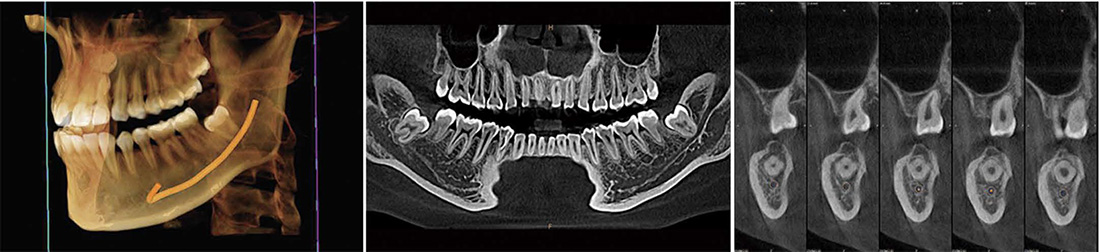

3D

Excelentes imágenes de TC

El gran campo de visión D14×10H puede satisfacer todas las necesidades del departamento clínico dental. Se pueden obtener imágenes de toda la dentición, incluida la articulación temporomandibular, en una sola exploración.

Planificación de la cirugia de implantes

Representación del tubo neural

- Comprobar la dirección del tubo neural y su relación con la posición de las muelas del juicio

- Comprobar la distancia entre el tubo neural y el implante para evitar que el implante toque el tubo neural

ATM bilateral

Con un gran campo de visión de 14*10, el modo ATM facilita el diagnóstico médico de enfermedades de la articulación temporomandibular.